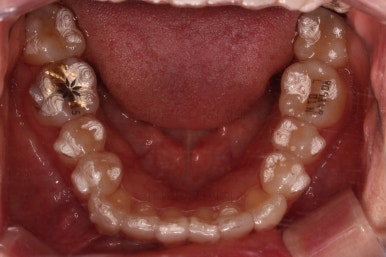

4. 마무리

철사교정과 마찬가지로 앞니쪽에 유지장치를 구성하고 치료를 종료합니다.

매우 가지런해졌고요.

맞물림도 좋아졌고, 중앙선도 잘 맞춰졌습니다.